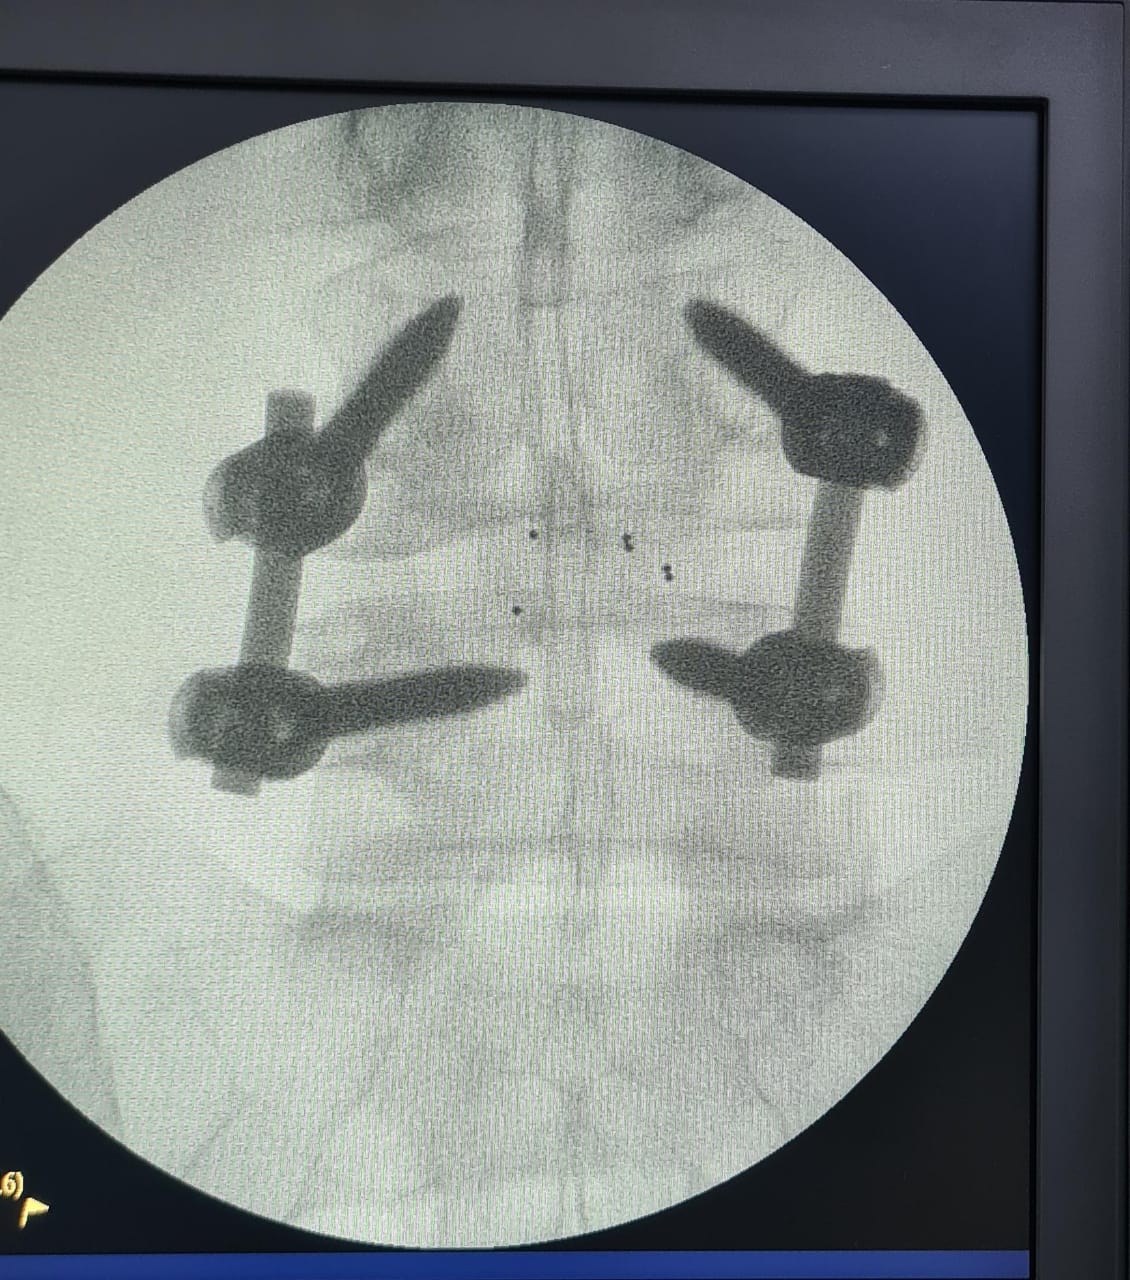

“Fueron tres tipos de exposiciones. Una de ellas es la cirugía en vivo, donde realizamos dos procedimientos en pabellón, acompañados por destacados especialistas, el Dr. Carlos Zanardi, presidente de la Sociedad de Neurocirugía de Buenos Aires, Argentina y el Dr. Cristiano Meneses, director del Instituto de Columna de Brasil”, precisó el Dr. Muñoz.

A continuación, compartimos las fotografías enviadas por el Dr. Avaria a la Sociedad de Neurocirugía de Chile: